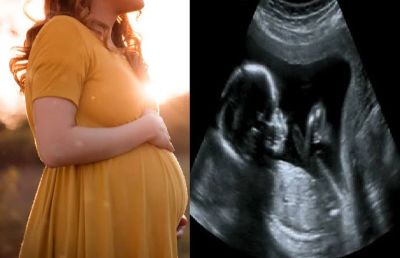

स्वास्थ्य एवं परिवार कल्याण मंत्री दिनेश गुंडूराव ने कहा कि स्वास्थ्य एवं पुलिस विभाग के अधिकारी female foeticide को रोकने के लिए सभी आवश्यक कदम उठा रहे हैं। उन्होंने मण्ड्या जिले के पांडवपुर, बेलगावी और कोडुगू सहित कई स्थानों पर अल्ट्रासाउंड स्कैनिंग केंद्रों पर छापे मारे हैं। वे अदालतों में मामले व आरोप पत्र दायर करने के साथ-साथ सभी सुरागों पर काम कर रहे हैं। कन्या भ्रूण हत्या को रोकने के लिए कानूनों को मजबूत करने की संभावनाओं पर मंथन जारी है।